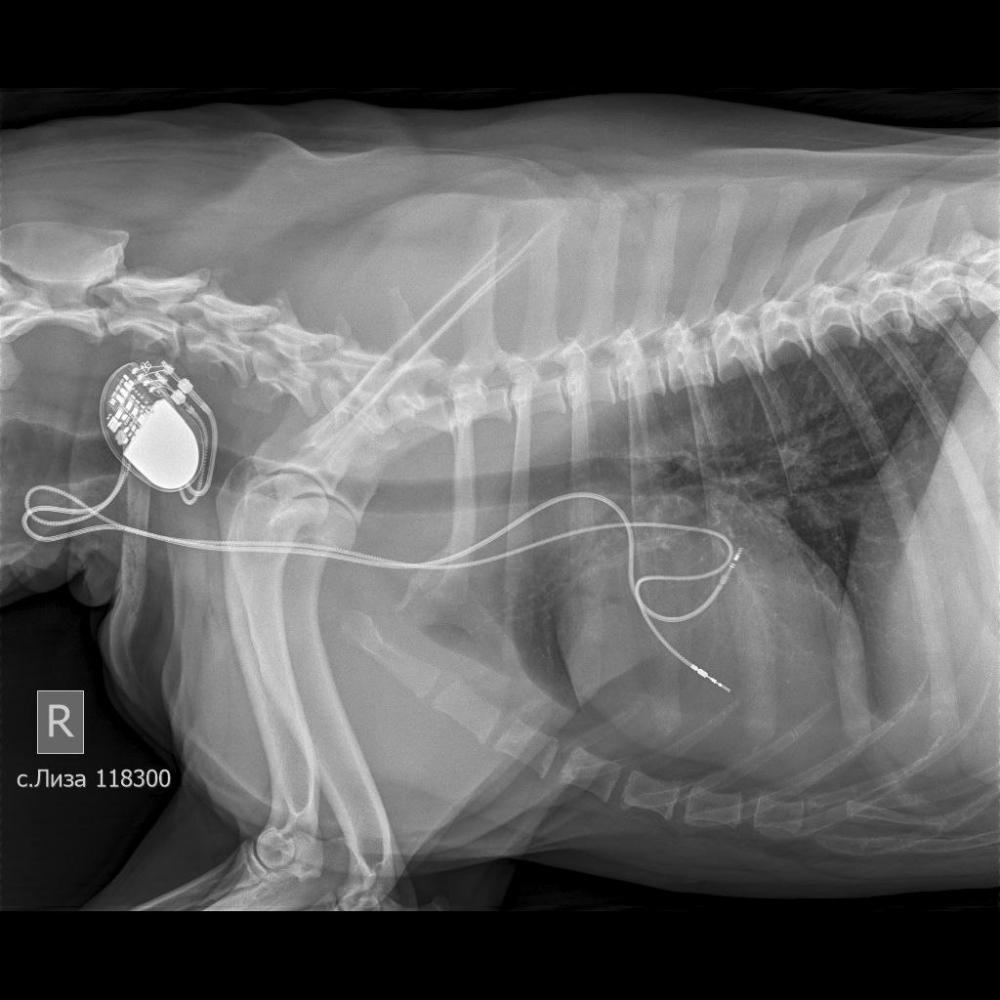

Дарья Г Опубликовано 17 января Автор Опубликовано 17 января мы уже сделали операцию, я купила стетоскоп, послушала сама и поняла, что с таким сердцем долго не живут. вот теперь месяц реабилитации, надо следить, чтобы не бегала, давать антидепрессанты, от которых она спит. 2

Дарья Г Опубликовано 17 января Автор Опубликовано 17 января да, опыта у всех мало, таких операций в нашей стране сделали около сотни в лучшем случае. ей поставили кардиостимулятор, который передает на желудочки входящий ритм, потом она два дня была в стационаре, потом я ее забрала и теперь надо месяц следить чтобы она не прыгала, чтобы, не дай бог, эти электроды не сместились, я за сутки уже такой невроз заработала на этой почве, бегаю за ней со стетоскопом, проверяю ее сердце, корю себя что она у меня по столам лазит, хотя это запрещено. спасибо всем за добрые пожелания! 1